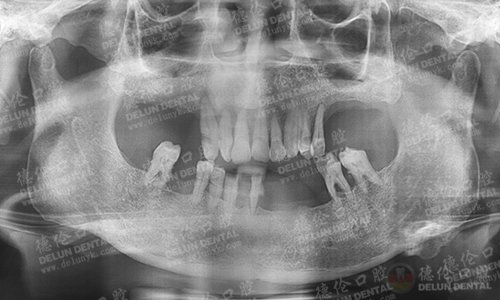

牙齿症状:上排牙缺失8颗,下排牙缺失7颗。

李老伯口腔全景X光片